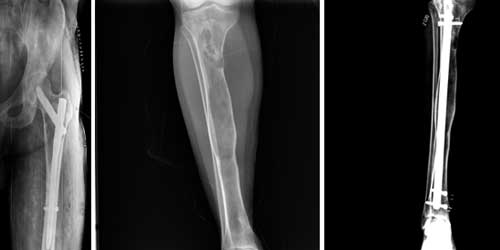

Osteosarkom

Kemiğin en sık 2. kanseridir. Yıllık insidansı 4-6: 1 milyondur. Çoğu primer dediğimiz kendiliğinden ortaya çıkarken nadiren sekonder dediğimiz Paget hastalığı ya da radyasyon zemininde gelişebilir.